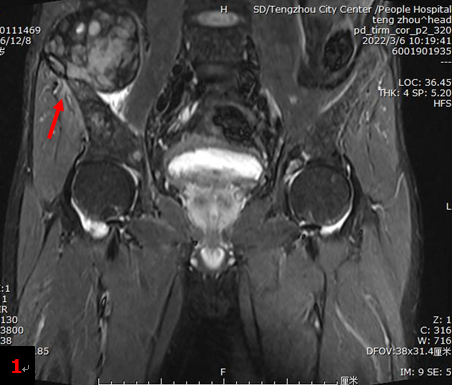

中年男性,一周前外院CT檢查提示:雙腎結(jié)石、雙腎積水、右輸尿管結(jié)石、雙側(cè)髂骨異常。入院后行雙髖關(guān)節(jié)MRI檢查提示:右髂骨翼上方肌肉內(nèi)異常信號腫塊影,間葉組織來源?(圖1箭)雙側(cè)髂骨翼及雙側(cè)股骨上段異常信號。為明確病情行18F-FDG PET/CT檢查。

全身多發(fā)骨骼(包括四肢骨和中軸骨)骨質(zhì)破壞(圖2),部分伴軟組織腫塊形成,顯像劑攝取明顯增高,其中右側(cè)髂骨SUVmax約13.0。